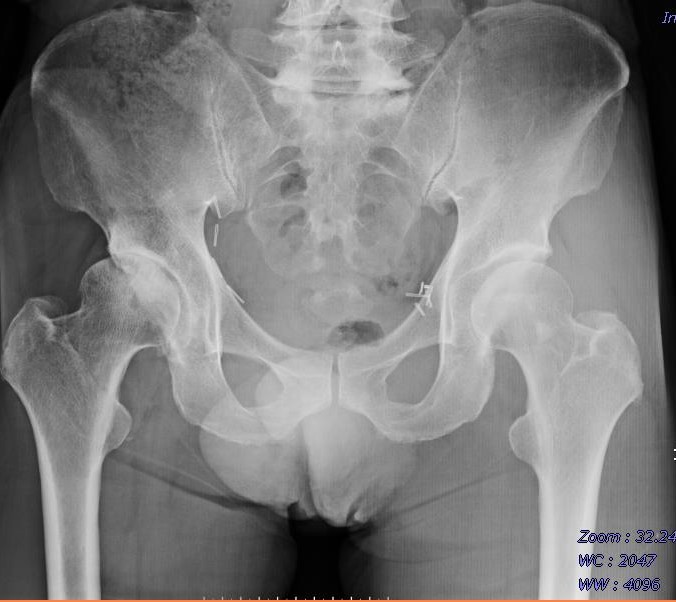

66歳 男性 右変形性股関節症

術前

術後

70歳 男性 右変形性股関節症

60歳 男性 右変形性股関節症